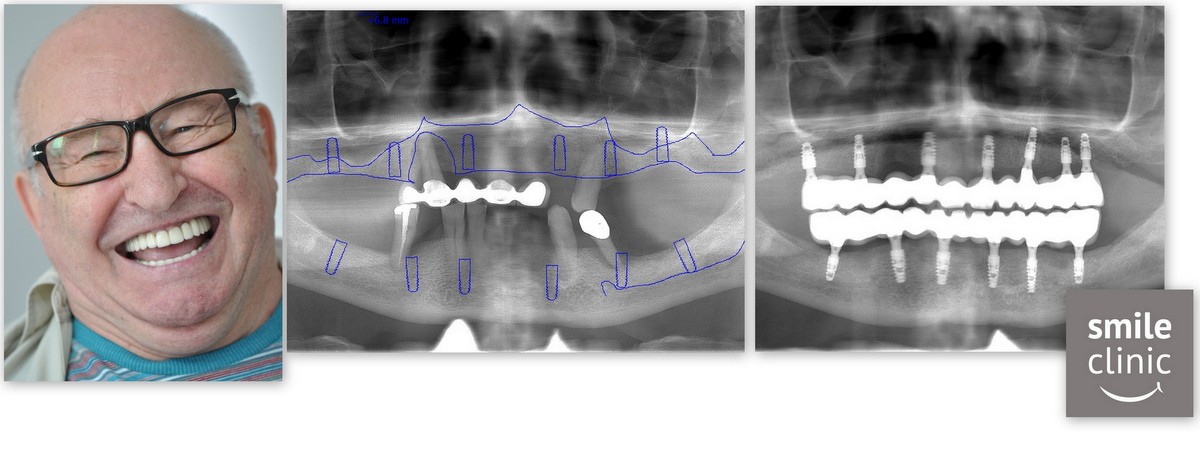

Michael wanted to have both his upper and lower dental implants done on his first visit to us.

After the first consultation with our head implantologist and treatment planing with our treatment coordinator we began the dental treatment on the very next day after his arrival.

First we placed 6 lower jaw dental implants and 7 upper jaw dental implants were placed on the next days. We find this currently to be the best way how to plan the treatment for the patient so that we can reduce chair time for them.

A full arch of immediate temporary teeth were placed on his first visit to us as well, so that he could go home an immediately start smiling from day 1.

From start to finish this whole upper and lower jaw reconstruction took 5 months to complete.